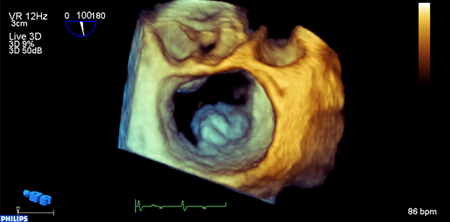

Prolapso do folheto P2 da valva mitral: visualização 3D

Do acervo de Prakash P. Punjabi

Veja esta imagem em contexto nas seguintes seções:

Regurgitação mitral